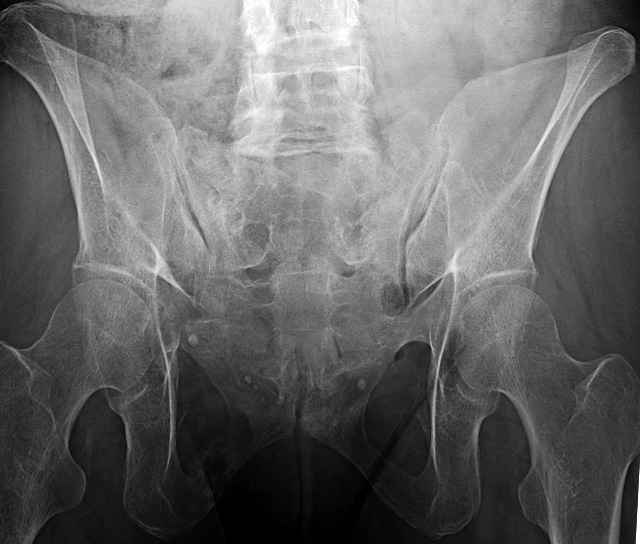

Here are a recent patient’s example slides...

54 yo Female Fell c/o Pain

Initial Films

?Instability on Exam - Limited by Pain

NonOp Initial Mgmt

3 Months After Fall

Continued Pain & Immobility

(+) Instability to Compressive Manual Exam